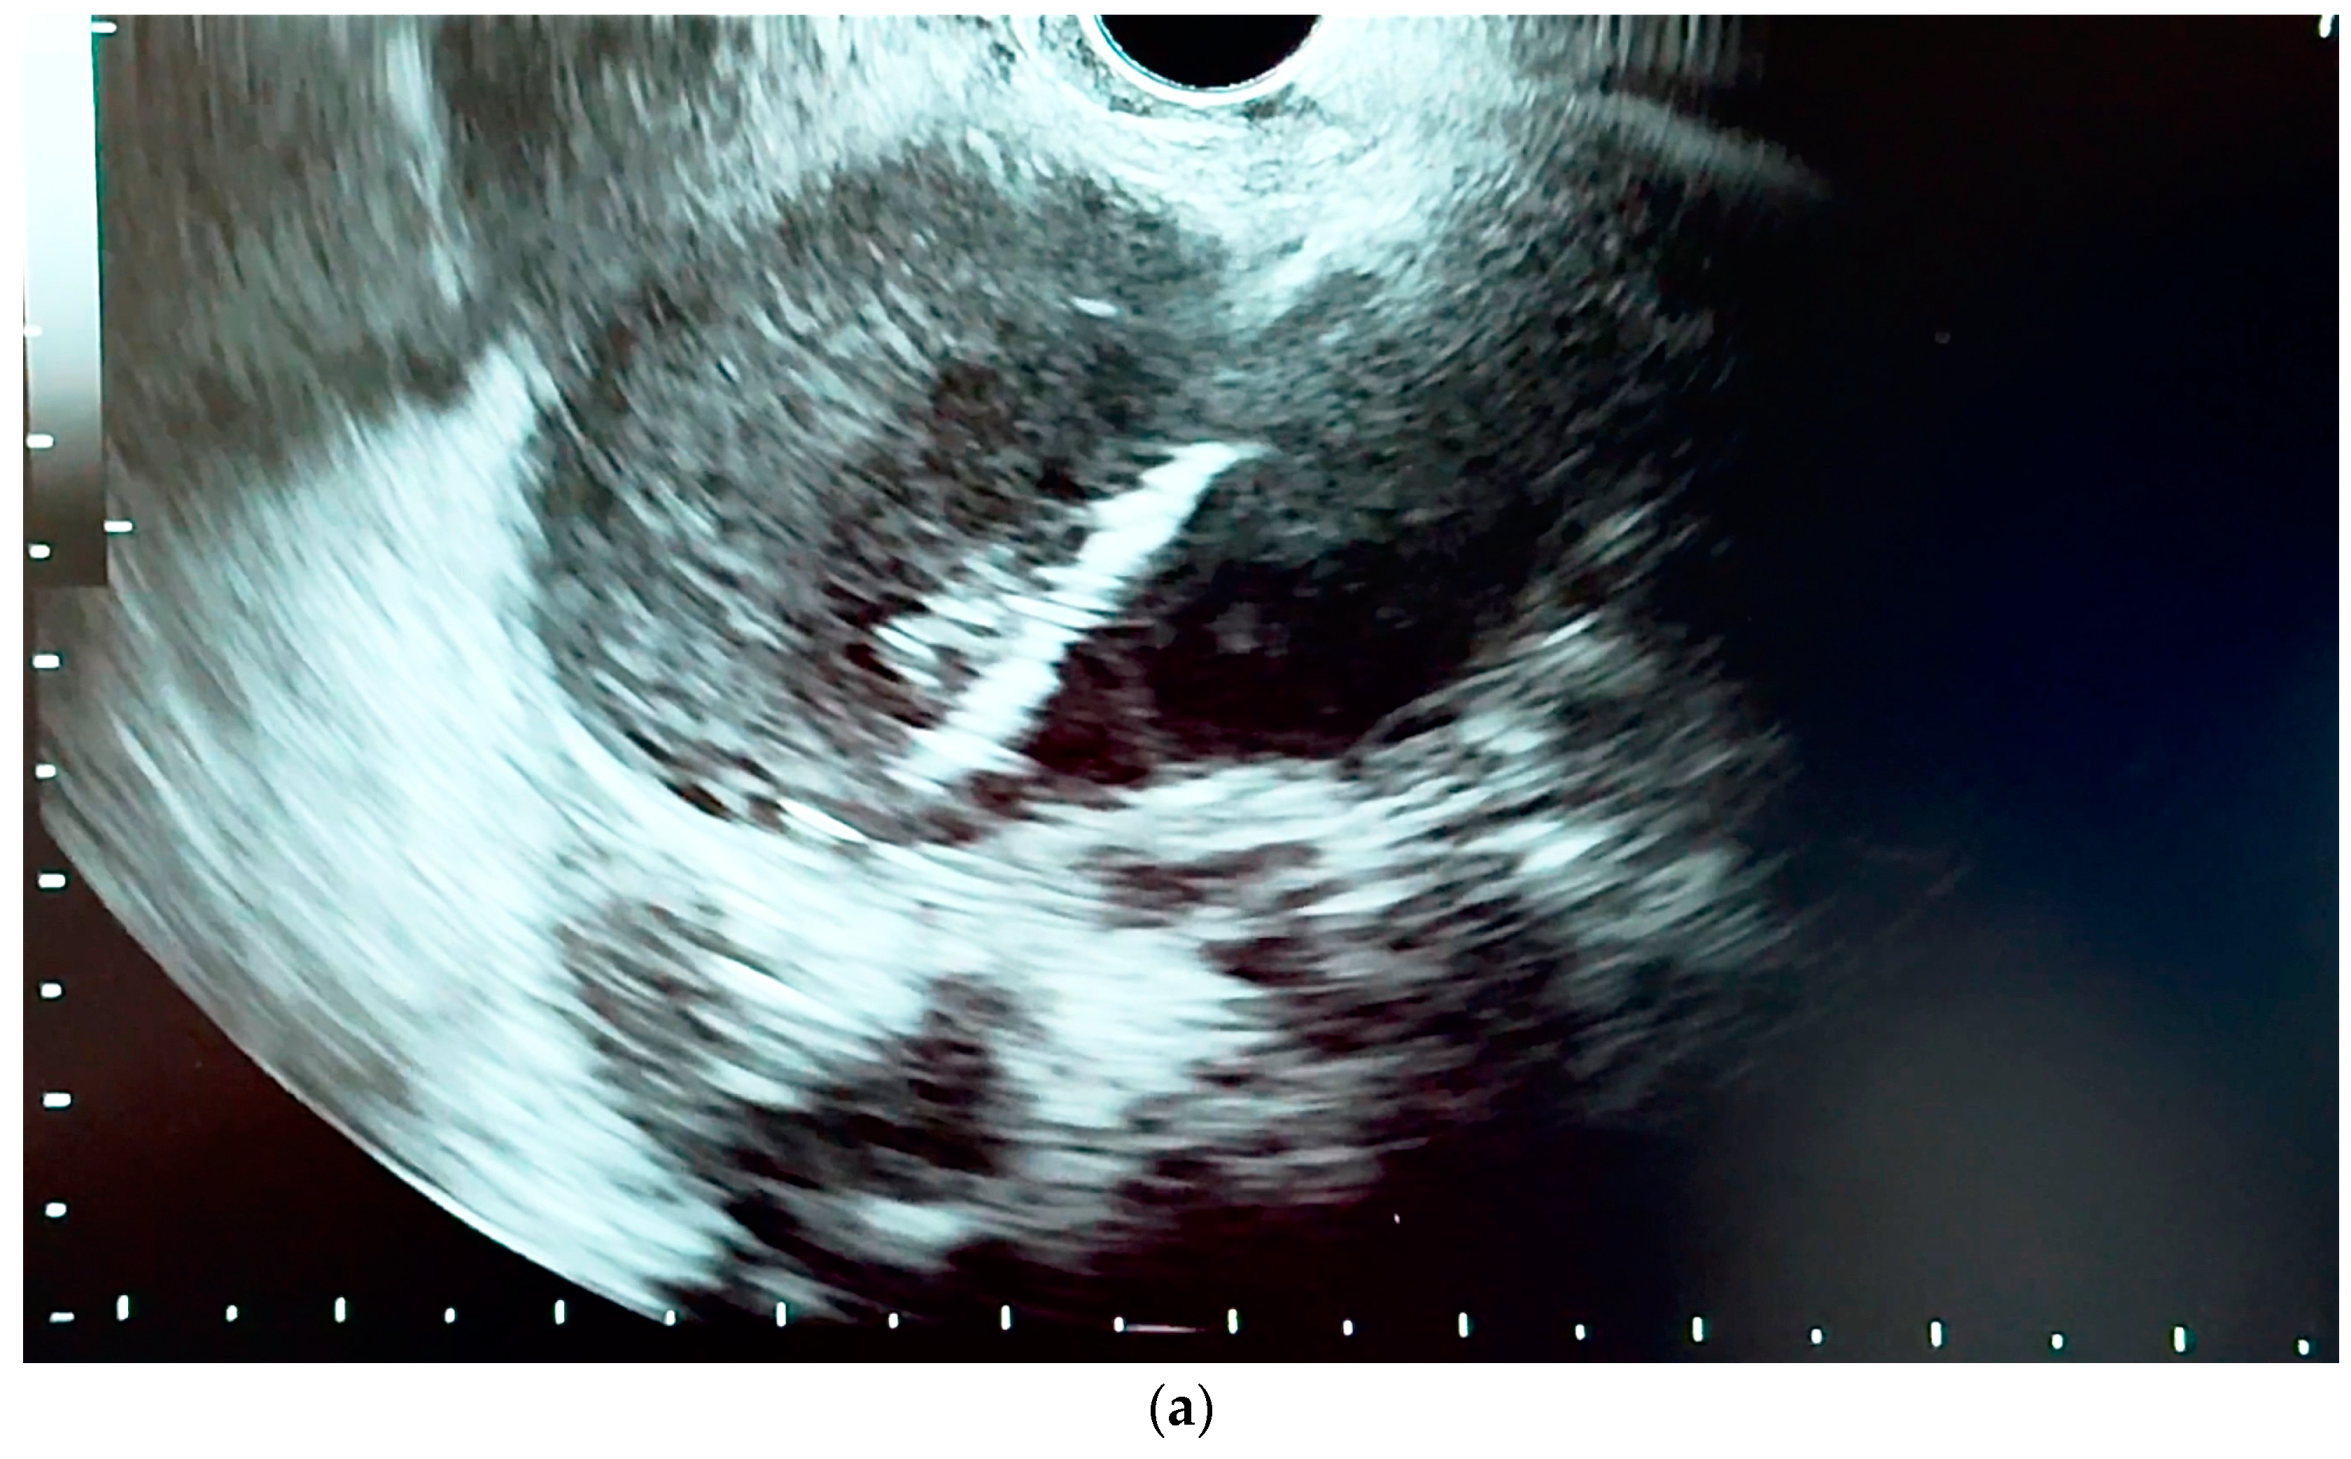

6.4.1. Endoscopic Ultrasound (EUS)

- Orzan, R.I.; Pojoga, C.; Agoston, R.; Seicean, R.; Seicean, A. Endoscopic Ultrasound in the Diagnosis of Extrahepatic Cholangiocarcinoma: What Do We Know in 2023? Diagnostics 2023, 13, 1023. [Google Scholar] [CrossRef] [PubMed]

- Otsuka, Y.; Kamata, K.; Hyodo, T.; Chikugo, T.; Hara, A.; Tanaka, H.; Yoshikawa, T.; Ishikawa, R.; Okamoto, A.; Yamazaki, T.; et al. Utility of contrast-enhanced harmonic endoscopic ultrasonography for T-staging of patients with extrahepatic bile duct cancer. Surg. Endosc. 2022, 36, 3254–3260. [Google Scholar] [CrossRef] [PubMed]